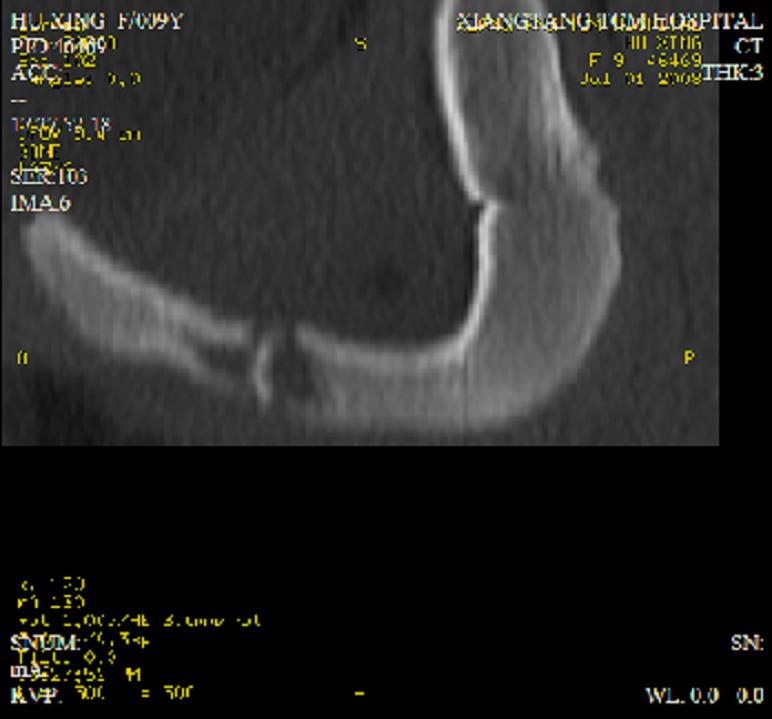

以下是引用dyqct在2008-7-2 15:38:00的发言:[br]左坐骨与耻骨交界处膨胀性溶骨性病变,周围软组织略肿胀,边界不清。[br]发生在这个年龄组该部位最常见的一种发育变异,可以出现此种改变。另外感染不除外,建议定期复查。